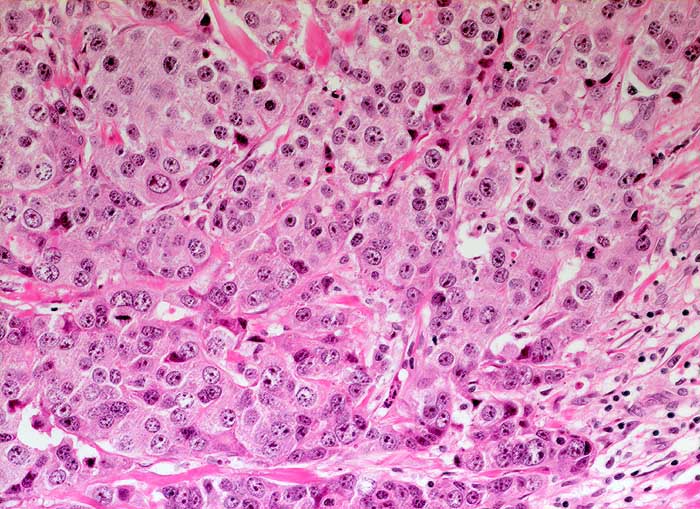

Das invasive Mammakarzinom zeigt zytologisch eine homogene Population maligner Zellen. Typischerweise sollten die Ausstriche zellreich sein und alle vorhandenen Zellen sollten maligne aussehen. Wenn man atypische Zellen suchen muss, ist der Ausstrich nicht diagnostisch für ein Karzinom, kann aber gleichwohl verdächtig sein. Die malignen Zellen sind in lockeren Gruppen gelagert und viele liegen einzeln. Crowding, Zellkannibalismus und Kernmolding sind gute Hinweise auf Malignität. Myoepithelien sind meistens aber nicht immer abwesend. Mammakarzinomzellen sind eher monomorph und deutlich grösser als normale duktale Epithelien. Zellkerne, die grösser sind als zwei Erythrozytendurchmesser, sind tumorverdächtig. Fast immer sind Kerbungen der Zellmembran nachweisbar. Das Chromatin ist im Gegensatz zu anderen Adenokarzinomen fein granulär und gleichmässig im Kern verteilt. Nukleolen sind meist unscheinbar. Makronukleolen sprechen für ein invasives Karzinom.

Die Kohäsivität ist das wichtigste Kriterium zur Feststellung des Differenzierungsgrades. Bei hoch differenzierten Karzinomen finden sich Verbände, bei wenig differenzierten liegen die Tumorzellen vermehrt einzeln. Wenig differenzierte Karzinome zeigen gesteigerte Kernatypien und der Hintergrund ist eher detritisch aufgrund ausgedehnter Tumornekrosen.

Unten werden Beispiele von einem hochdifferenzierten und einem wenig differenzierten Mammakarzinom gezeigt.